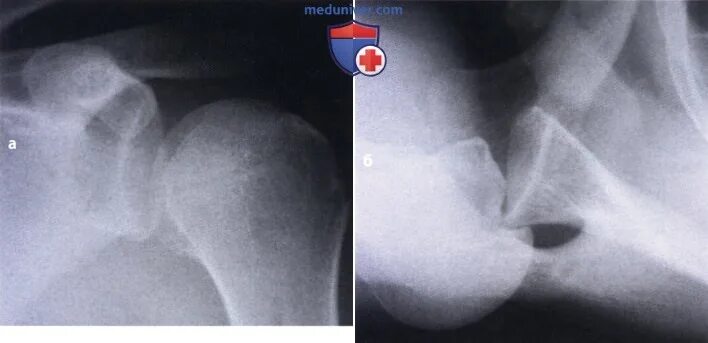

Операция на плечо привычный вывих